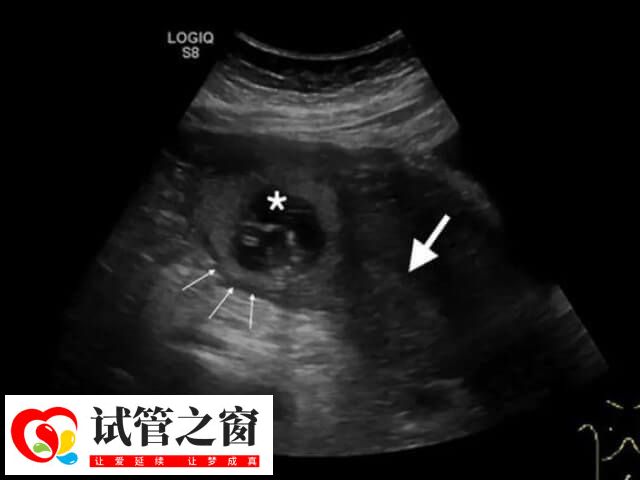

医生将胚胎移植到女性患者宫腔后,胚胎会在宫腔中处于游走状态,在经过几天时候后才会进行着床。而着床的位置是根据每个患者的不同宫腔环境有所差异,至于胚胎着床过程是怎样,如下所示:

1、一般在胚胎移植后的1至2天内,它会在子宫内游走,充分的吸收营养,继续分裂,成为1个有头有尾的细胞分裂的囊胚;

2、在移植后的3-7天,它会长出1个小尾巴,在子宫腔内找到一个舒服的位置,如子宫体前壁、后壁、侧壁这些位置,钻进子宫壁内,从而完成着床;

3、一般在移植后的8天,胚胎就会整个陷入子宫内,由卵巢的黄体分泌HCG,在移植后的14天左右,就可以用早孕试纸检测尿HCG,或者抽血查HCG的水平了解妊娠的情况。